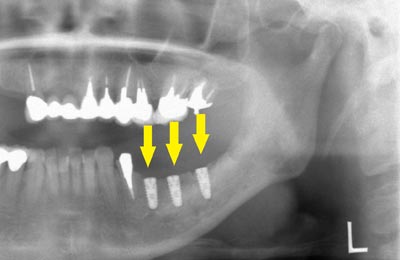

インプラント埋入後のレントゲン写真です。骨の高さが十分に確保されたので、神経を傷つけることなく、インプラント埋入手術ができました。

インプラント埋入後のレントゲン写真です。骨の高さが十分に確保されたので、神経を傷つけることなく、インプラント埋入手術ができました。